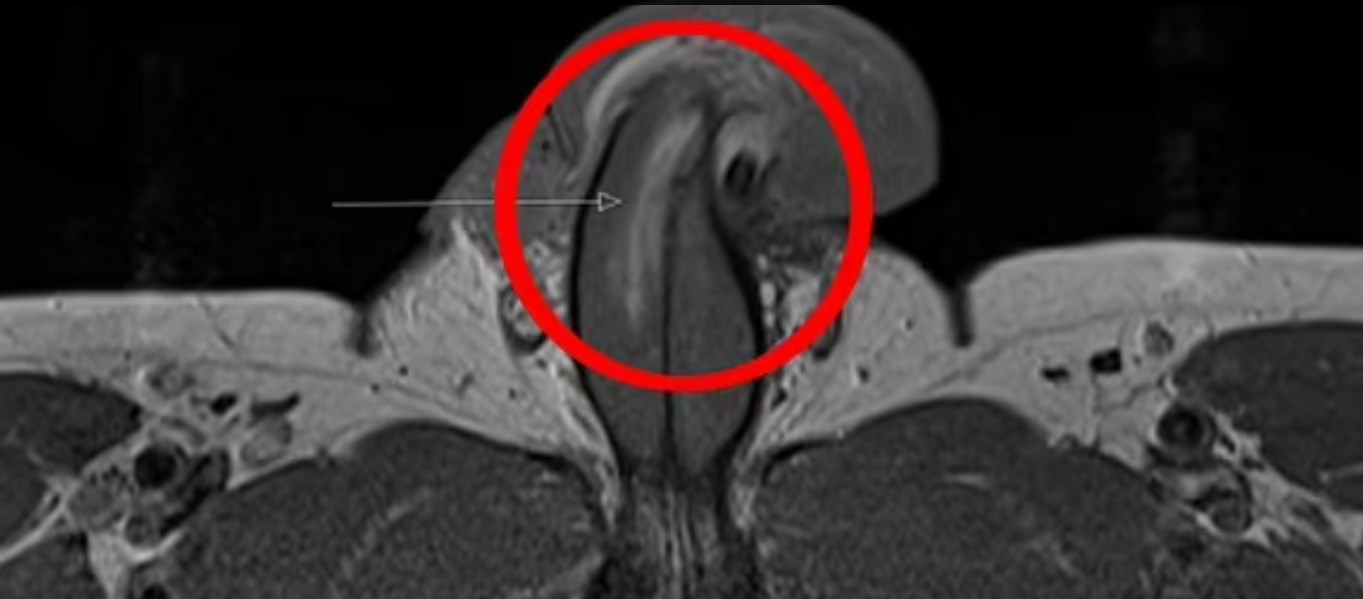

Είπαν ότι όλα τα κατάγματα του πέους που είχαν καταγραφεί στο παρελθόν ήταν οριζόντια. Αλλά σε αυτή την περίπτωση χωρίζει το tunica albuginea – το προστατευτικό στρώμα γύρω από τον στυτικό ιστό που αντλεί αίμα σε αυτήν την περιοχή. Ο γιατρός είπε ότι δεν ακούστηκε ήχος «αναδυόμενου» όταν συνέβη το σπάσιμο, το οποίο συμβαίνει όταν τα κατάγματα είναι οριζόντια. Τα σηραγγώδη σώματα συγκρατούνται από μια ισχυρή μεμβράνη που ονομάζεται ινώδης χιτώνας. Όταν ένας άνδρας υποφέρει από κάταγμα πέους, ουσιαστικά έχει σπάσει αυτή η ισχυρή μεμβράνη.